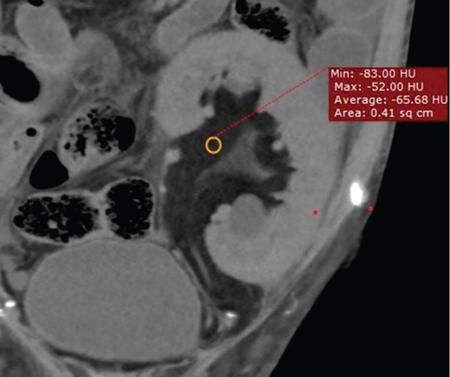

RRL is a more aggressive form of RSL usually occurring unilaterally. There is marked proliferation of fatty tissue within the renal sinus and hilum extending to the perirenal space. This occurs usually secondary to destruction or atrophy of renal parenchyma due to longstanding inflammation. This condition most commonly follows calculus disease and also has been associated with aging, renal TB and postrenal transplantation. As in RSL compensatory or inflammatory fatty proliferation secondary to renal loss are postulated as mechanisms of injury. It has been postulated that renal calculi trigger a process of hydronephrosis and chronic inflammation which in turn results in parenchymal atrophy and fibrofatty replacement in the sinus. Unlike RSL patients with RRL are usually symptomatic and present with recurrent flank pain, fever, and weight loss and mass per abdomen. RRL appears as a hyperechoic mass in the renal fossa often extending into the perinephric space. The kidney is often enlarged with atrophic parenchyma with or without visualization of a calculus. Helps make accurate diagnoses. It confirms the fatty nature of the pelvic lesion and differentiates it from nonfatty lesions of the pelvis (Fig. 10.12.2.6.2). CT scan defines the extent of the fatty proliferation in the renal fossa and in perinephric area, detects associated conditions such as hydronephrosis, renal/ureteric calculi and helps assessing the degree of parenchymal atrophy. Perirenal fat stranding and dilated, thick-walled and enhancing ureters have also been described.

Computed tomography